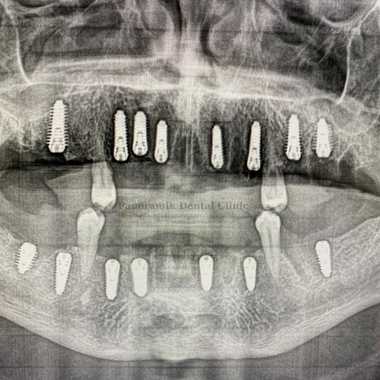

All on Eight Implants Technique

What Is All on 8 Implantation? How Is It Used?

All on 8 implants technique are used when a person is missing teeth. After implantation, a temporary denture is placed if necessary. The gums heal in about a week, and it takes three to six months of time for the bone to fully heal.

All on 8 implant is a dental procedure where eight implants are fixed in the tooth row, it is mainly used for people who have lost 80% of their teeth.

The all on 8 implant technique allows 28 teeth to be placed in the entire jaw. With this system, chewing comfort is improved because the load is distributed over the entire jaw. In addition, it is possible to segment the patient's teeth, which means that if a problem arises in the future, it will be easy to identify where it is located and treat it in a short period of time.

Although the implant treatment is done in one day, a period of 3 to 6 months is required for overall follow-up. In addition, this period depends on your oral and dental health. If you have gum problems or require additional procedures such as root canal treatment, sinus lift, bone grafting, you will need to stay longer. The length of treatment with All on 8 implants depends on the patient's oral and dental health. All on 8 implantation consists of two stages. In the first stage, the existing teeth are treated and the implants are placed. In the second stage, after 3, 4 or 6 months, abutments on the implants and crowns are placed.